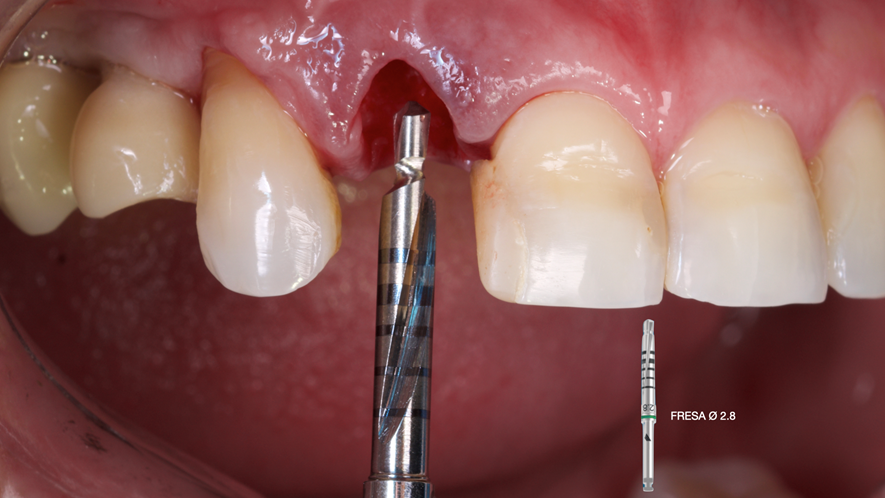

Este trabalho tem como objetivo relatar um caso clínico de exodontia minimamente invasiva de um incisivo lateral superior com fratura radicular, realizando implante imediato em alvéolo pós-extração, enxerto de tecido conjuntivo subepitelial e osso bovino liofilizado para preenchimento de GAP, prontamente à instalação de pilar reto e provisório imediato.